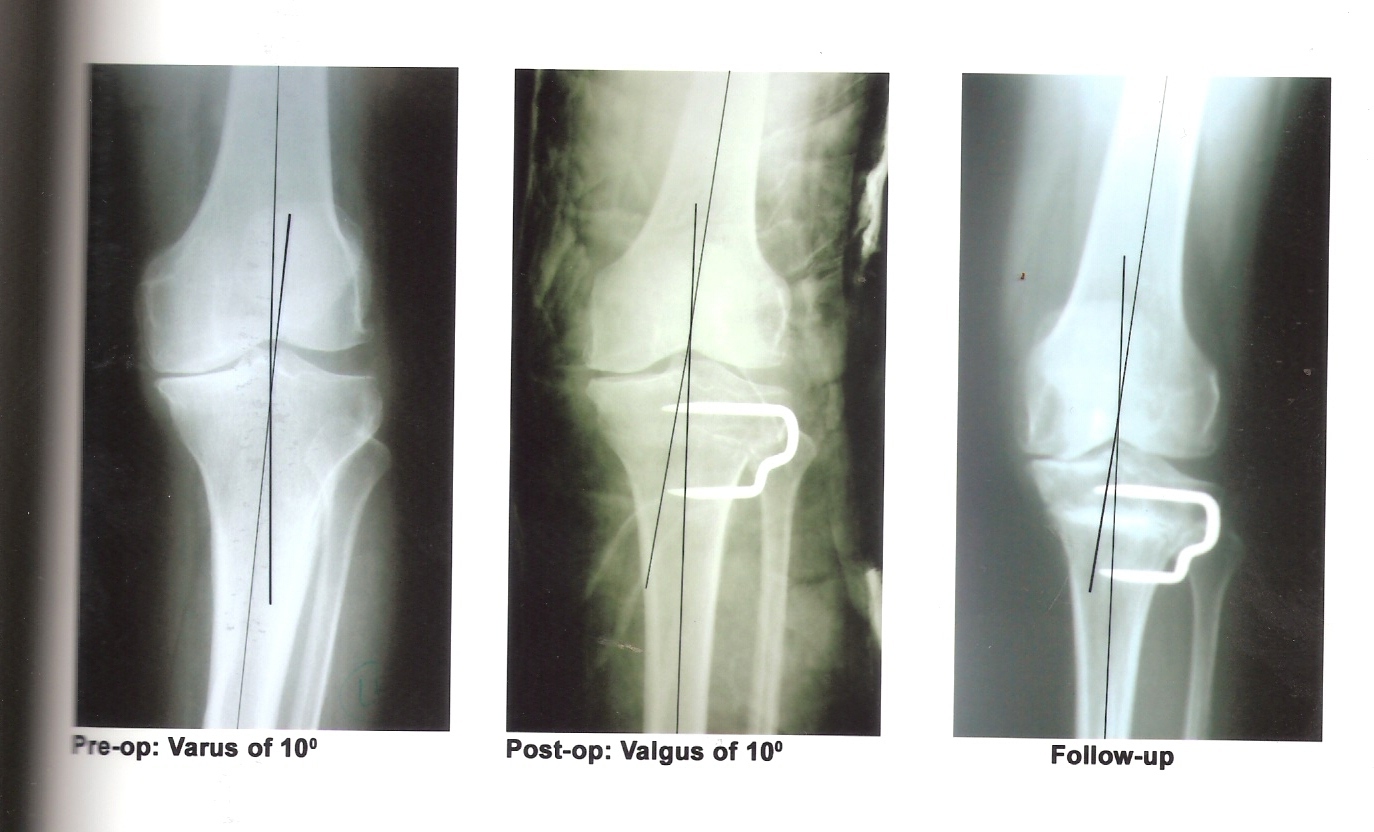

Introduction: Osteoarthritis of the knee is a common orthopaedic condition. Medial compartment osteoarthritis results from undue stress on the medial compartment of the knee joint following varus deformity. High tibial osteotomy (HTO) has been a long-standing treatment for osteoarthritis of the medial compartment of the knee. Although knee replacement has gained wide popularity for its treatment, still HTO is a good and cost effective procedure for young patients having good range of motion and uni-compartmental involvement. Objective: To evaluate the results of HTO in medial compartment osteoarthritis. Methods and Material: This study was conducted in a tertiary care teaching hospital of North India over a period of 3 years. The patients with disabling knee pain due to medial compartment osteoarthrosis with genu varus deformity refractory to conservative treatment were treated by High Tibial Osteotomy. Results: Overall 40 patients with medial compartmental osteoarthritis were treated with HTO. Patients were evaluated for the severity of pain as per Visual Analogue Score (VAS). There was satisfactory pain reduction (up to 80%) in most of the patients. Conclusions: HTO is a good procedure for young patients with good range of motion and changes confined to one compartment only.